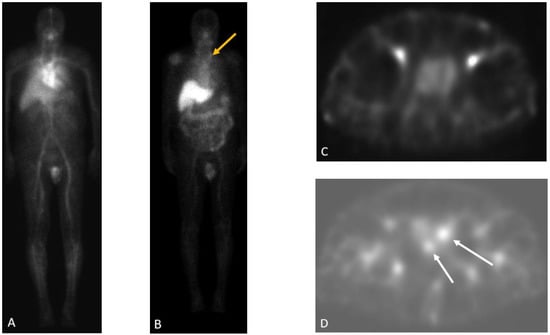

Detection of Loco-Regional Disease and Distant Metastases